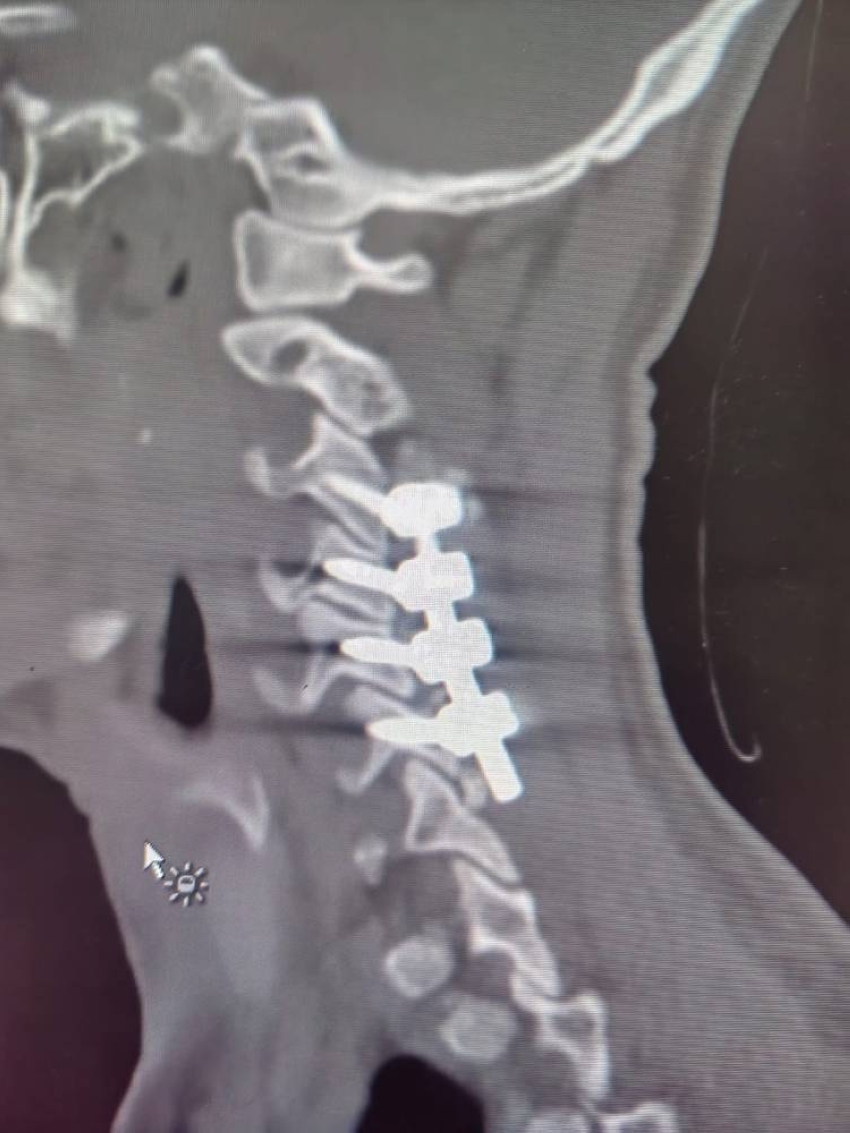

نجح الفريق الطبي في مستشفى الملك سعود بمحافظة عنيزة في إجراء تدخل جراحي نوعي ودقيق لتثبيت الفقرات العنقية من الخلف وتوسيع الحبل الشوكي، لمريض شاب يبلغ من العمر 26 عامًا، تعرض لإصابة بليغة إثر حادث سقوط، أسفرت عن شلل نصفي وتهديد مباشر لحياته.

وكان المريض قد نُقل إلى قسم الطوارئ وهو يعاني من شلل تام في الأطراف السفلية وضعف ملحوظ في الأطراف العلوية، وكشفت الفحوصات الطبية والأشعة التصويرية عن وجود كسور متعددة في الفقرات العنقية الرابعة والخامسة والسادسة من الجهتين الأمامية والخلفية، مع اقتراب خطير من الشريان الفقري، أحد الشرايين الرئيسية المغذية للدماغ، كما أظهرت النتائج وجود كدمة شديدة ونزيف في الحبل الشوكي عند مستوى الفقرات الثالثة والرابعة والخامسة، ما تطلّب تدخلاً فوريًا لتفادي مضاعفات تهدد حياة المريض.

وخلال تدخل جراحي استمر قرابة ست ساعات، أجرى الفريق الطبي تثبيتًا للفقرات المصابة من الخلف، إضافة إلى توسيع الحبل الشوكي لتخفيف الضغط الناتج عن الكدمة والنزيف، وبالنظر إلى حساسية موقع الكسور وقربها من الشريان الفقري، تم التنسيق مسبقًا مع استشاري الأوعية الدموية في مستشفى بريدة المركزي ليكون على أهبة الاستعداد للتدخل الفوري عند الحاجة، إلا أن العملية -بفضل الله- تمت بنجاح ودون أي مضاعفات أو إصابة في الشريان.